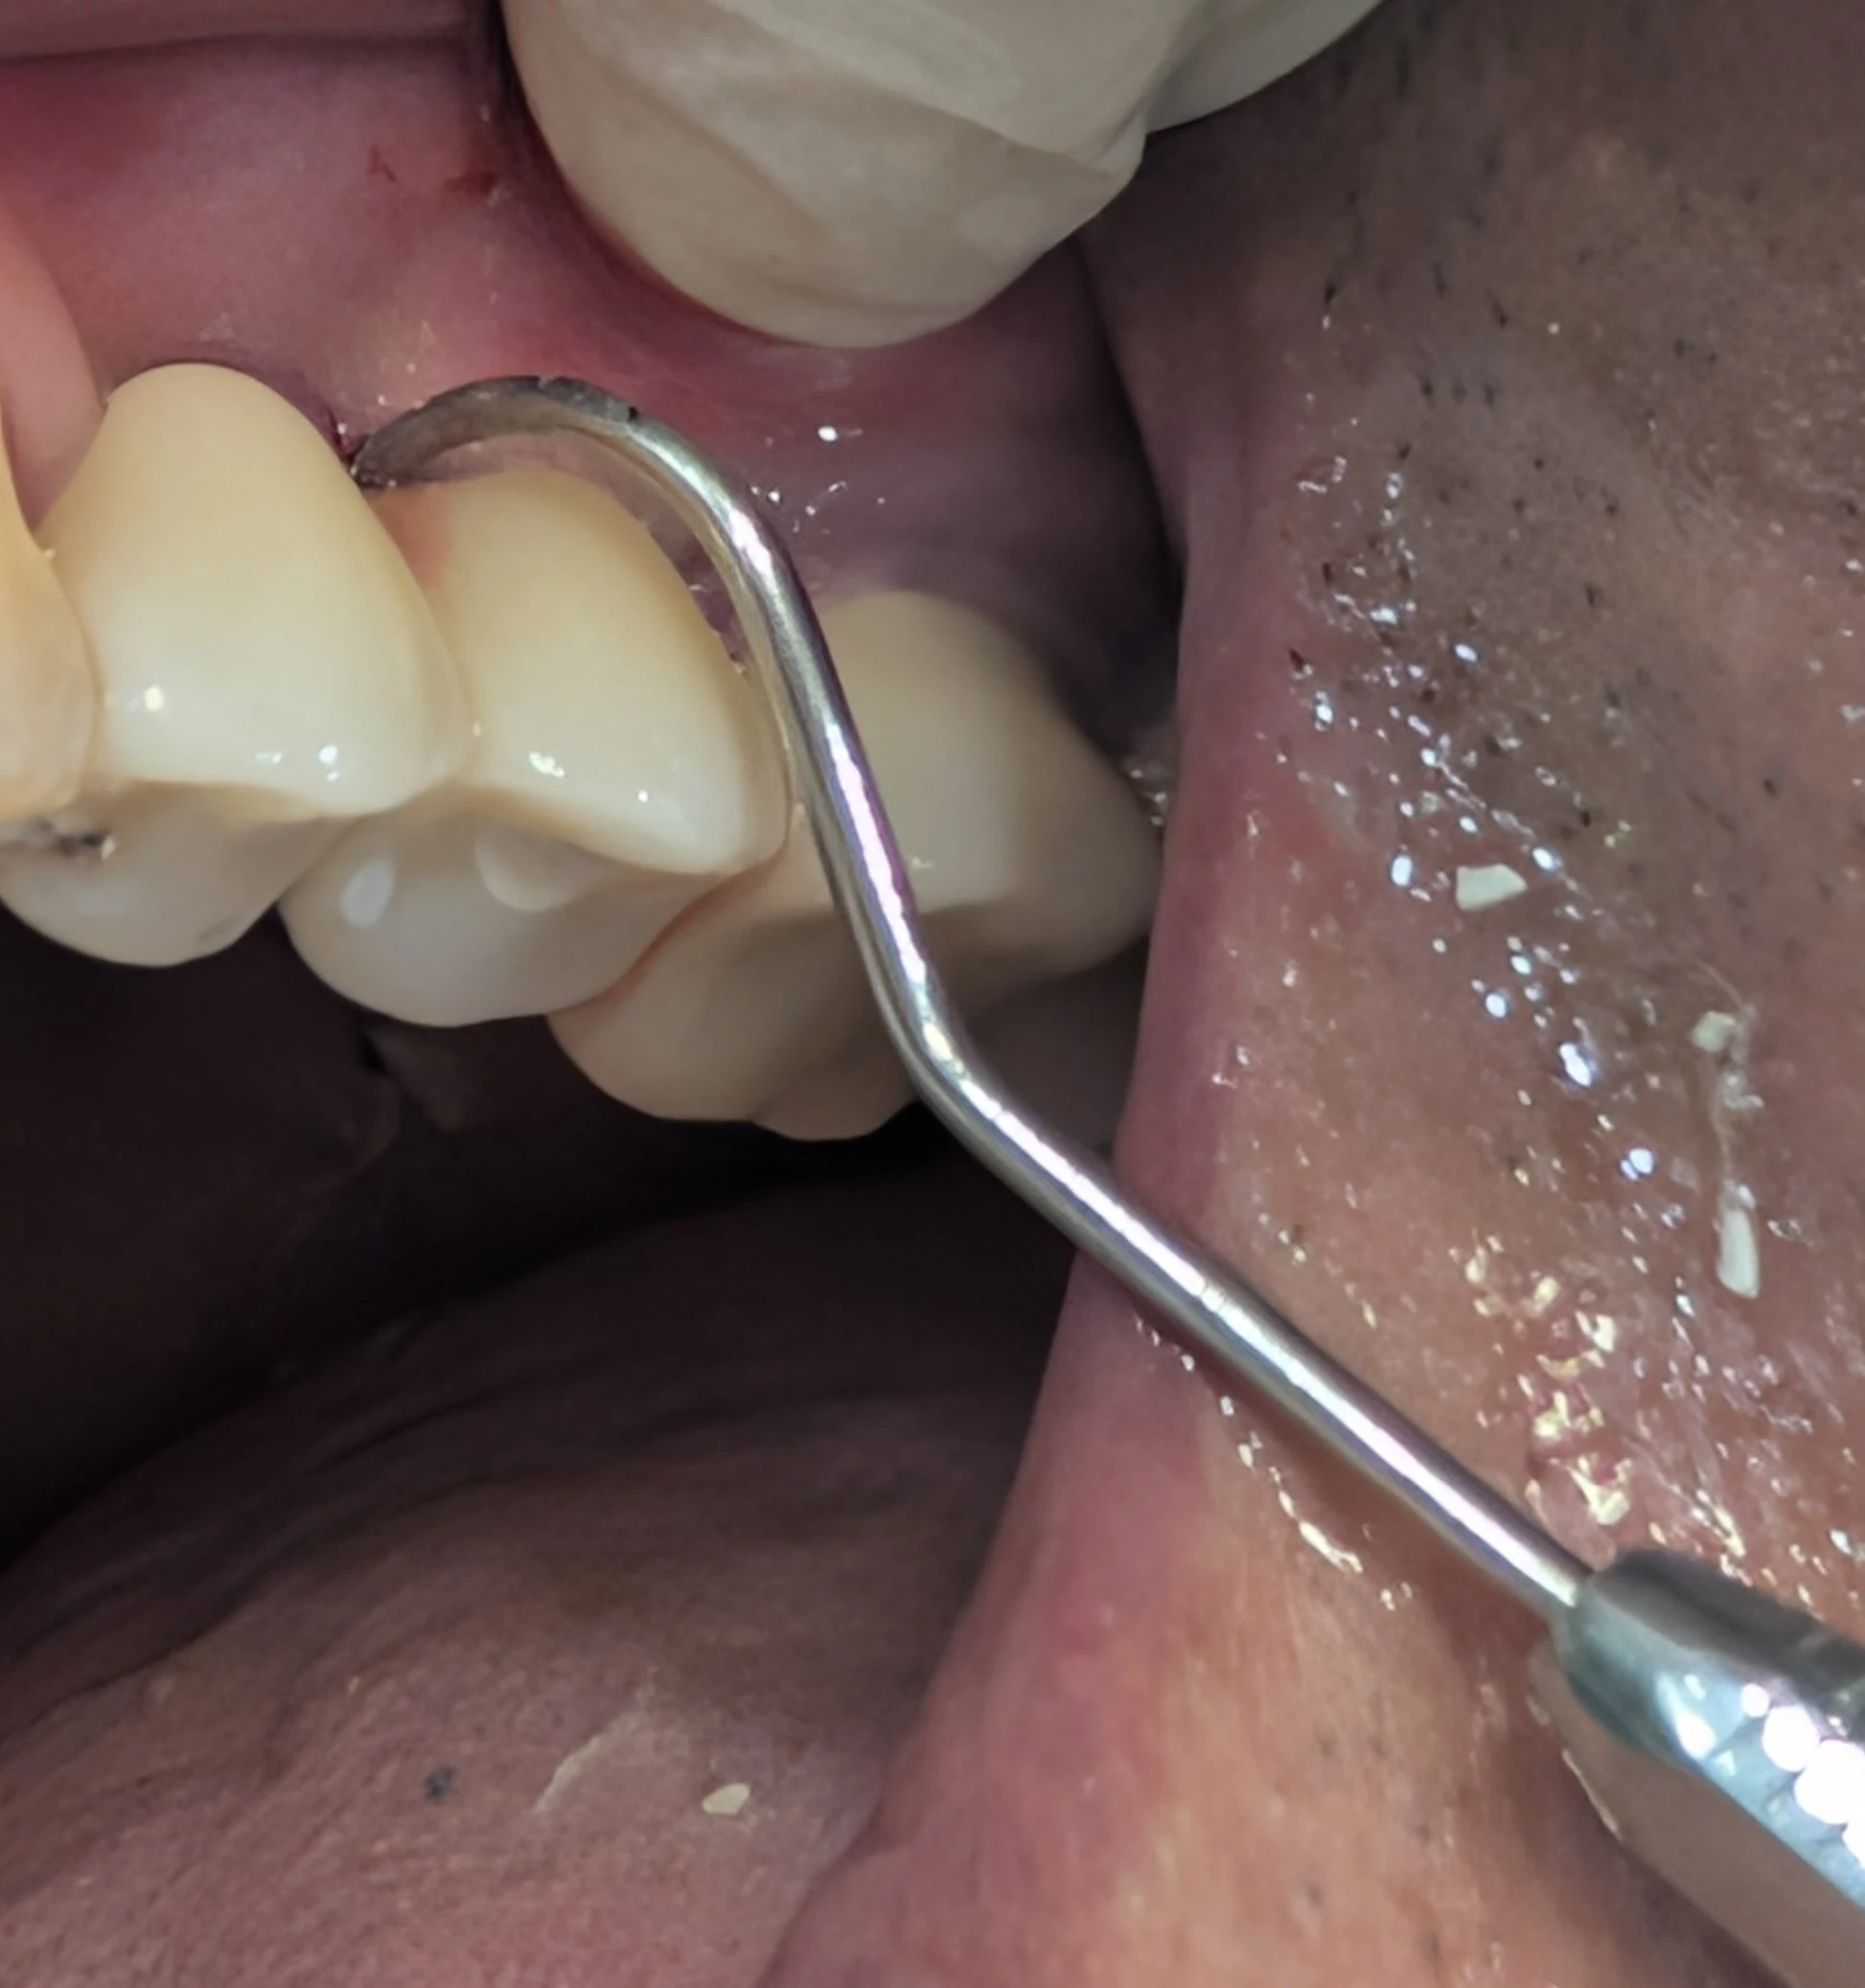

تست عبور سوند در ایمپلنت های اسپلینت شده

🔹 عبور سوند از امبراژور اسپلینت قبل از تحویل

وقتی روکش‌های ایمپلنت به هم اسپلینت هستند، باید با سوند از امبراژور بین آن‌ها عبور کنیم تا مطمئن شویم که یک مسیر واقعی و قابل‌استفاده برای بیمار وجود دارد.

اگر سوند عبور نکند ← یعنی مسیر بهداشتی وجود ندارد ← یعنی باید کانتور، امبراژور یا تماس‌ها اصلاح شوند.

عبور دادن سوند از امبراژور اسپلینت قبل از تحویل، یک تست ساده و حیاتی است که سرنوشت بیولوژیک ایمپلنت را تعیین می‌کند.